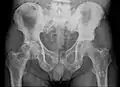

Radio du bassin d'un patient atteint d'un carcinome de la prostate : multiples métastases ostéocondensantes, en particulier sur le sacrum, mais aussi sur l'ilion surtout gauche (à dr. sur l'image), sur la pointe de l'ischion gauche, et sur le fémur proximal gauche. On détecte à l'occasion une arthrose de hanche droite (à g. sur l'image).

Radio du bassin avec métastases ostéolytiques. Les métastases sont sur les deux fémurs et sur le bassin lui-même.